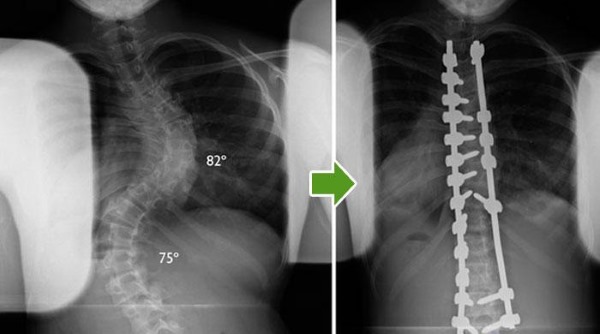

Оперативное вмешательство при сколиозе является одним из самых сложных и в то же время увлекательных аспектов хирургии позвоночника. Реконструкция может затрагивать практически всю длину позвоночного столба, особенно в случаях нейромышечных деформаций. Это действительно сложные ситуации.

Рентгеновский снимок до и после операции на сколиозе